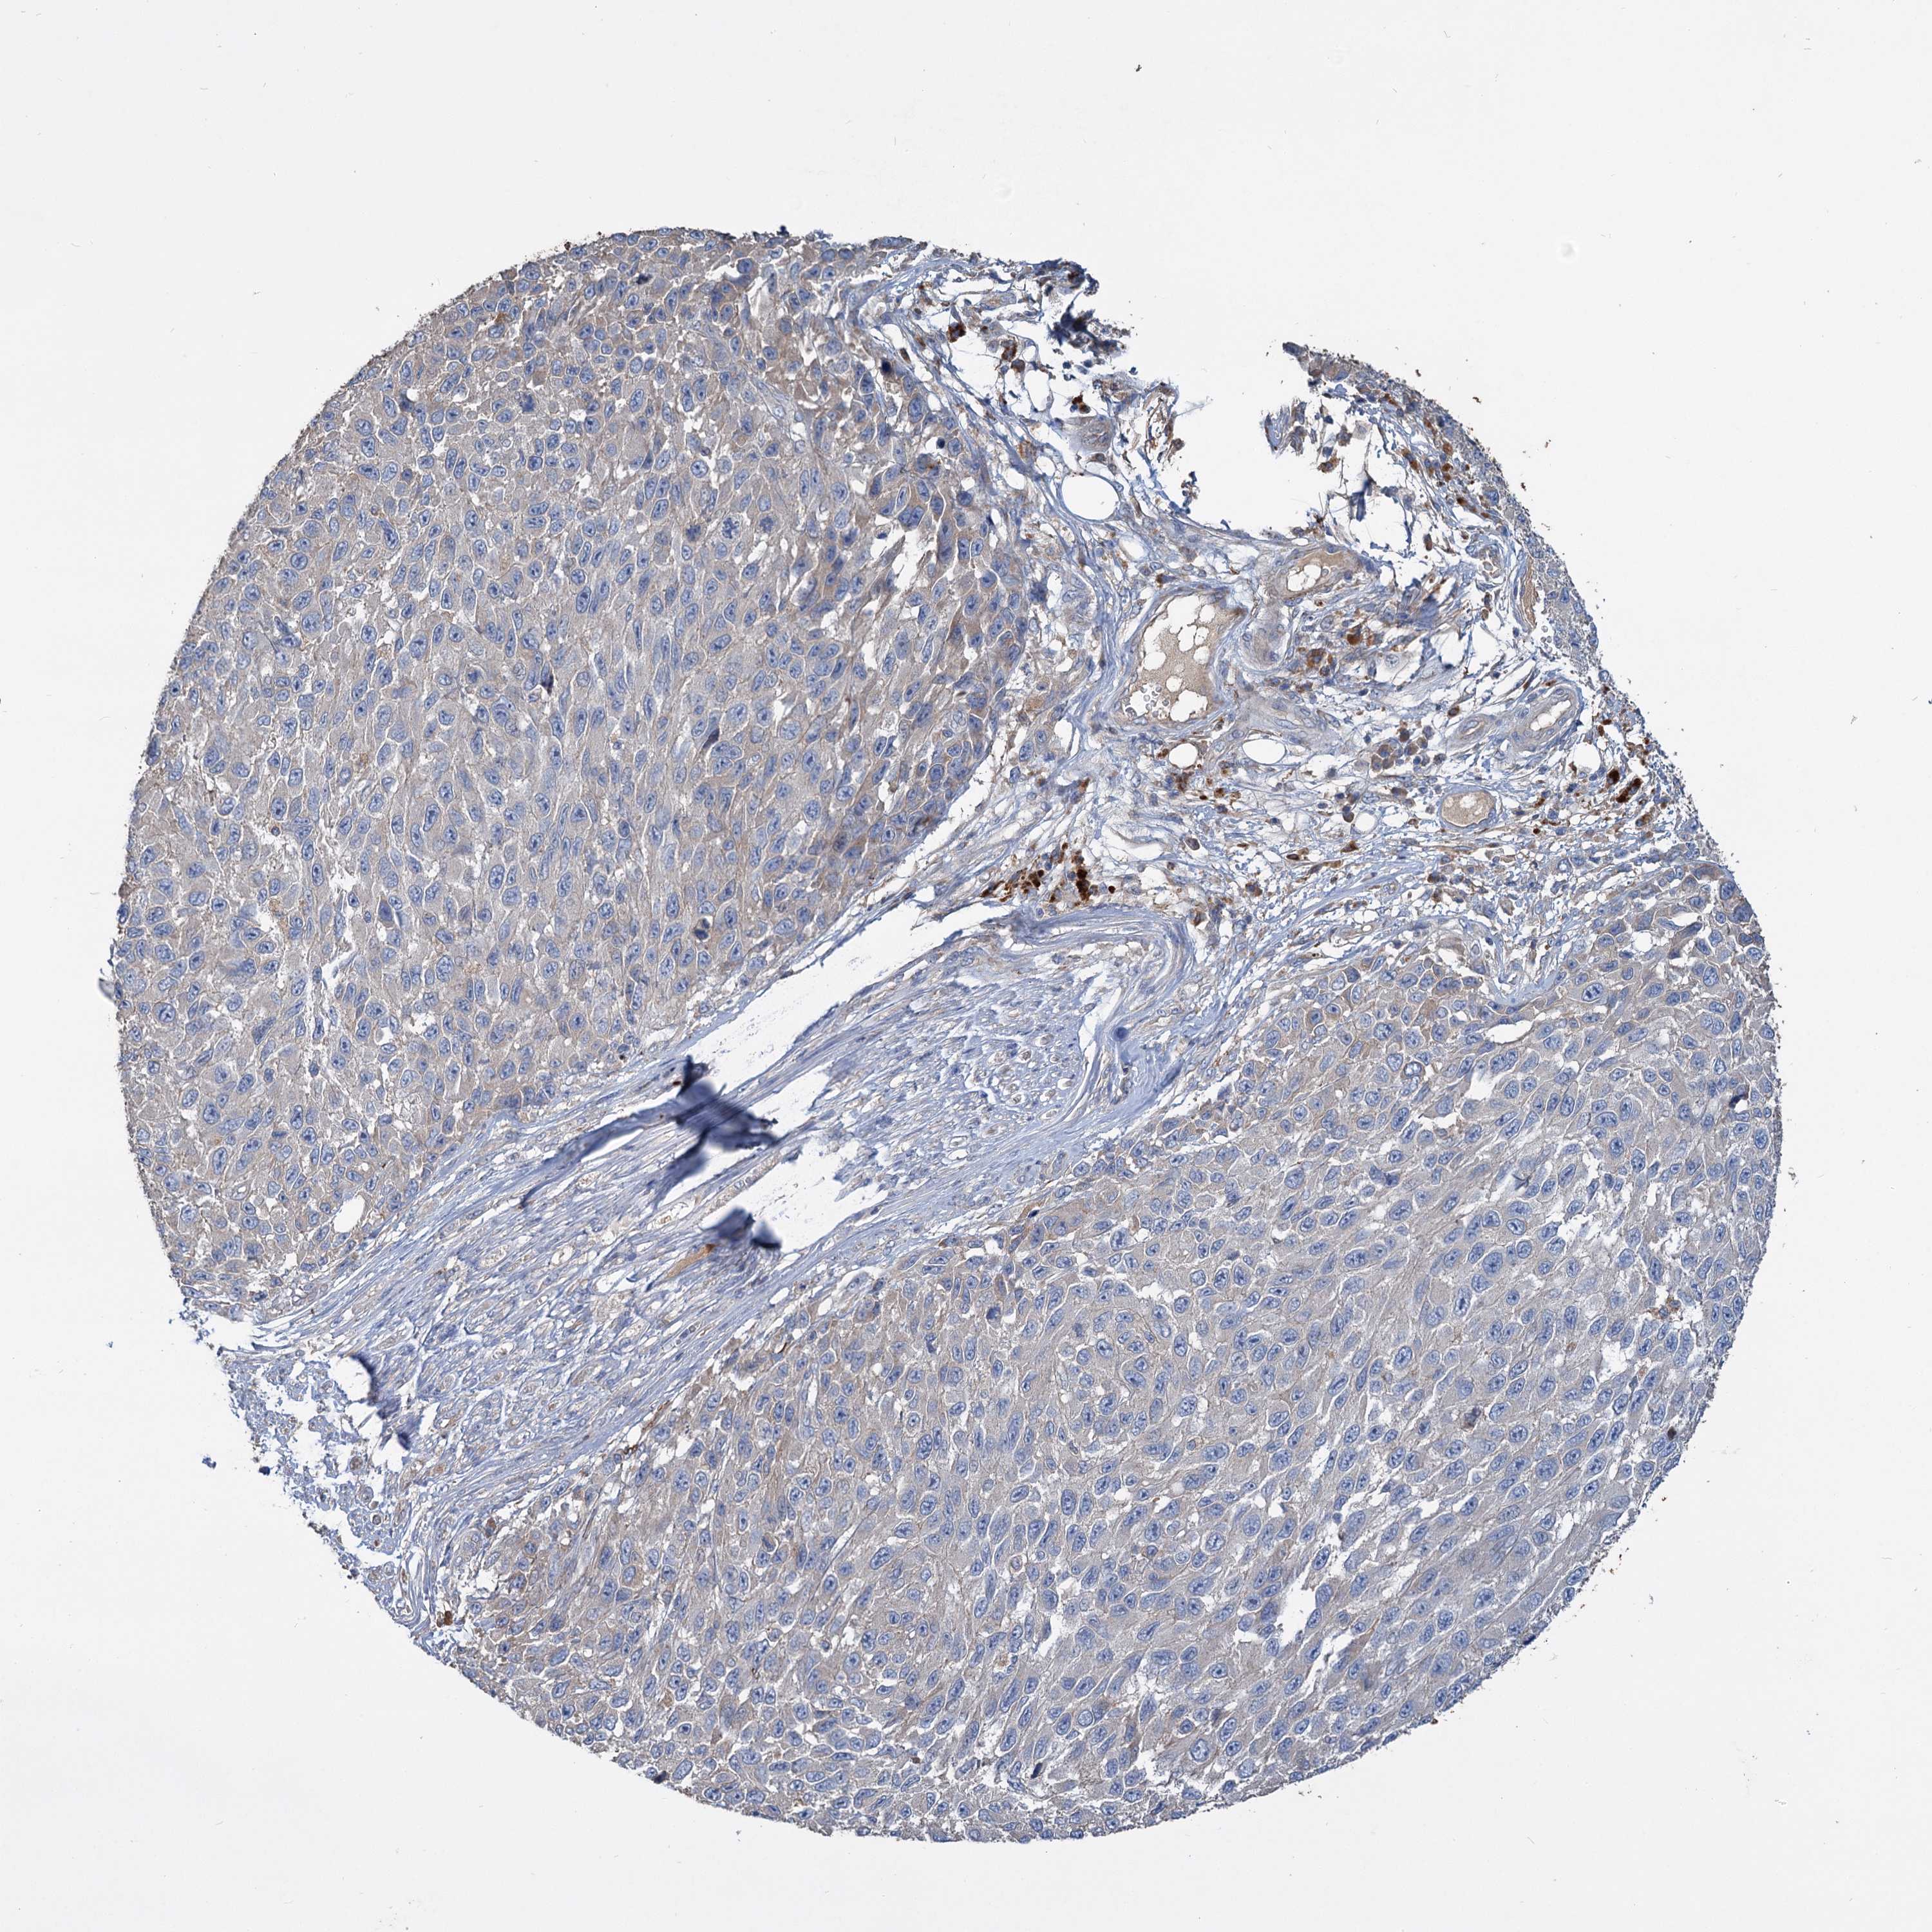

MELANOMA - Protein expressioni

A mouse-over function shows sample information and annotation data. Click on an image to view it in a full screen mode. Samples can be filtered based on level of antibody staining by selecting one or several of the following categories: high, medium, low and not detected. The assay and annotation is described here.

Note that samples used for immunohistochemistry by the Human Protein Atlas do not correspond to samples in the TCGA dataset.

Antibody stainingi

Antibody staining in the annotated cell types in the current human tissue is reported as not detected, low, medium, or high, based on conventional immunohistochemistry profiling in selected tissues. This score is based on the combination of the staining intensity and fraction of stained cells.

Each image is clickable and will lead to virtual microscopy that enables deeper exploration of all samples and also displays staining intensity scores, fraction scores and subcellular localization as well as patient and tissue information for each sample.

Antibody HPA038972

Staining

High

Medium

Low

Not detected

Intensity

Strong

Moderate

Weak

Negative

Quantity

>75%

75%-25%

<25%

None

Location

Nuclear

Cytoplasmic/membranous

Cytoplasmic/membranous,nuclear

Malignant melanoma, NOS

Malignant melanoma, Metastatic site